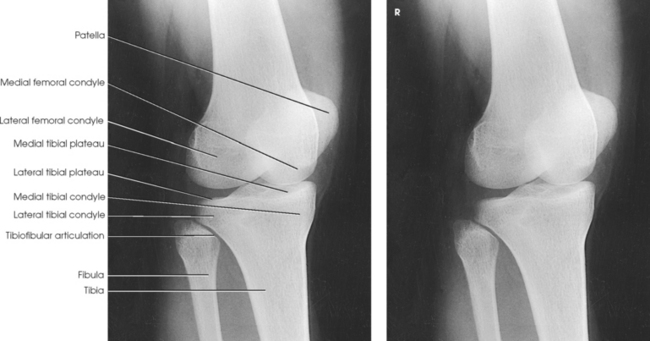

Structures shown: The resulting image shows an AP projection of the knee structures (Fig. 6-121).

Structures shown: The resulting radiograph shows a lateral image of the distal end of the femur, patella, knee joint, proximal ends of the tibia and fibula, and adjacent soft tissue (Fig. 6-126).

Structures shown: The resulting image shows an AP oblique projection of the laterally rotated femoral condyles, patella, tibial condyles, and head of the fibula (Fig. 6-132).

Structures shown: The resulting image shows an AP oblique projection of the medially rotated femoral condyles, patella, tibial condyles, proximal tibiofibular joint, and head of the fibula (Fig. 6-134).